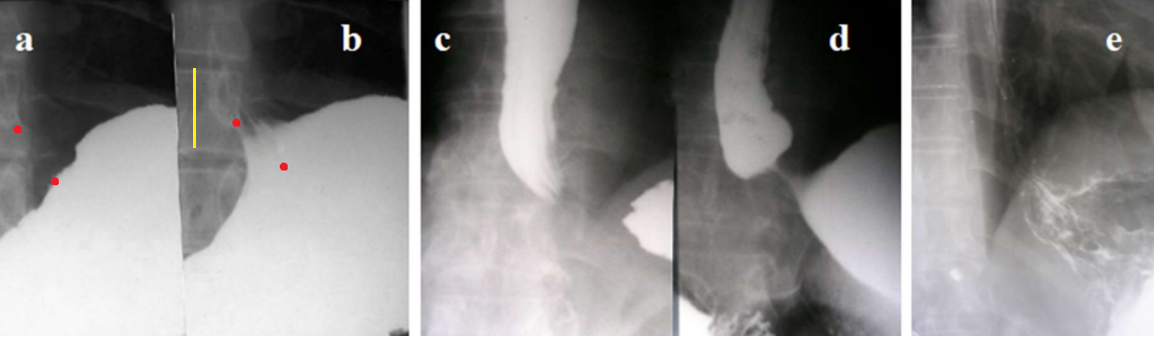

Figure 2. Radiographs of the EGJ in patients with GERD. (a). Before provocation. (b). During the water-siphon test, the LES between two red dots opened. Its length is 1.6 cm. The angle of His became obtuse. (c) Short LES without abdominal compression (2 cm vs 3.6 cm). (d) In the same patient with abdominal compression the LES length is 1 cm. (e) The opening of the LES in the form of a beak of the stomach is seen without provocation. The angle of His is obtuse.

These typical studies show that (1) Regardless of swallowing and pressure in the stomach, the distal point of the esophagus does not change its position, i.e., the length of the esophagus does not change; (2) Damage to the LES is manifested by its shortening mainly due to the opening of the intra-abdominal part of the LES. Those authors who call the "esophagus + LES" complex the esophagus come to false statements about shortening of the esophagus and displacement of the LES into the chest cavity [12]; (3). The degree of damage varies from slight shortening of the LES during maximum provocation to complete chalasia (gaping of the EGJ). During ontogenesis, the degree of damage to the LES increases. (4). In GERD, when the LES is unable to prevent reflux of gastric chyme, the pH of the chyme is not significant, since if it ensures the destruction of food proteins, it damages the wall of the esophagus. (5). An increase in the angle of His is not a cause of GERD, but evidence of LES shortening (Figure 3).